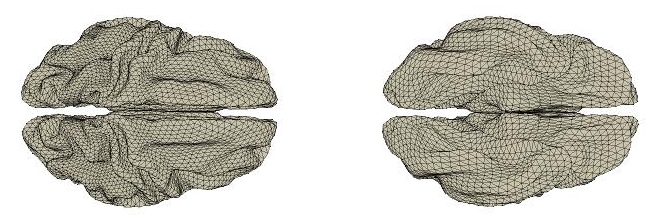

For a given , solving (7) with respect to will turn out to be equivalent to solving an inverse problem, which we discretize adopting a Mixed Finite Elements approach (Azzimonti et al., 2014). Specifically, consider now a triangulated surface , union of the finite set of triangles , giving an approximated representation of the manifold . We then consider the linear finite element space consisting of a set of globally continuous functions over that are affine where restricted to any triangle in , i.e.

In this section, we consider to be a 8K nodes triangular mesh, this time representing a template geometry of the cortical surface, which is shown in Figure 10. This contains only the geometric features common to all subjects. Moreover, each subject’s cortical surface is also represented by a 8K nodes triangular surface, which is used, together with the locations of the detectors on the sensors space, and the head model, to compute a forward operator for the th subject. The 8K nodes of each subject’s triangular mesh are in correspondence with the 8K nodes of the template mesh . This allows the model to be defined on the template .

Moreover, a surface based registration algorithm has been applied to register each of the extracted cortical surfaces to a triangulated template cortical surface, which is shown in Figure 10. Post registration, the triangulated template cortical surface is sub-sampled to a 8K nodes surface. Moreover, the nodes on the cortical surface of each subject are also sub-sampled to a set of 8K nodes in correspondence to the 8K nodes of the template. For each subject, a matrix, representing the forward operator, has been computed with FieldTrip (Oostenveld et al., 2011) from its head surface, cortical surface and sensors position. Such a matrix relates the vector-valued signals in , on the nodes of the triangulation of the cerebral cortex, to the one detected from the sensors, consisting of 248 magnetometer channels.